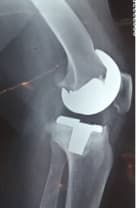

Тохиолдол танилцуулга 3.

Өвчтөн: M, 73 настай, эмэгтэй

Урьд нь хийгдсэн мэс заслын түүх: 2013 онд өвдөгний хиймэл үе суулгах мэс засал хийлгэсэн. Мэс заслын дараа халдварын хүндрэл гарсан.

Хоёрдахь мэс засал: Хиймэл үеийг авч, оронд нь антибиотиктэй цемент, төмөр бэхэлгээ хийсэн. Мэс заслын дараа үрэвсэл намдсан. Үрэвслийн улмаас ясны том хэмжээний дутмагшил үүссэн.

Сэргээн засах мэс засал: Зүүн дунд чөмөг-өвдөгний хавдрын протез суулгах мэс засал

Эмнэлэгт хэвтсэн ор хоног: 10

Үе дайрсан ясны анхдагч хавдар, ясны дутмагшлын үед хийгдэх мэс засалimage13

Зураг 1. Мэс заслын дараах рентген зураг: артродез буюу “үегүйжүүлэх” мэс засал.

Үе дайрсан ясны анхдагч хавдар, ясны дутмагшлын үед хийгдэх мэс засалimage14

Зураг 2. Мэс заслын үеийн фотозураг. Дунд чөмөг-өвдөгний хавдрын протез

Өвдөгний үений шөрмөсөн холбоосууд үрэвслийн улмаас бүрэн гэмтсэн Дунд чөмөг - шилбэ ясны 3 зэргийн дутмагшилтай учир дунд чөмөг-өвдөгний хавдрын протез сонгон суулгасан. Энэ дунд чөмөг-өвдөгний хавдрын протезын онцлог нь шилбэ болон дунд чөмөгний хэсэг нь хоорондоо давхар холбогдох нугас буюу hinge system-тэй юм. Hinge system нь үений холбоосын үүргийг гүйцэтгэн – үе хоорондын зайг барих, үений тогтвортой байдлыг хангах зорилготой.

Үе дайрсан ясны анхдагч хавдар, ясны дутмагшлын үед хийгдэх мэс засалimg15Үе дайрсан ясны анхдагч хавдар, ясны дутмагшлын үед хийгдэх мэс засалimg16

Зураг 3. Мэс заслын дараах рентген зураг. Эгц урд, хажуугаас авсан байдал